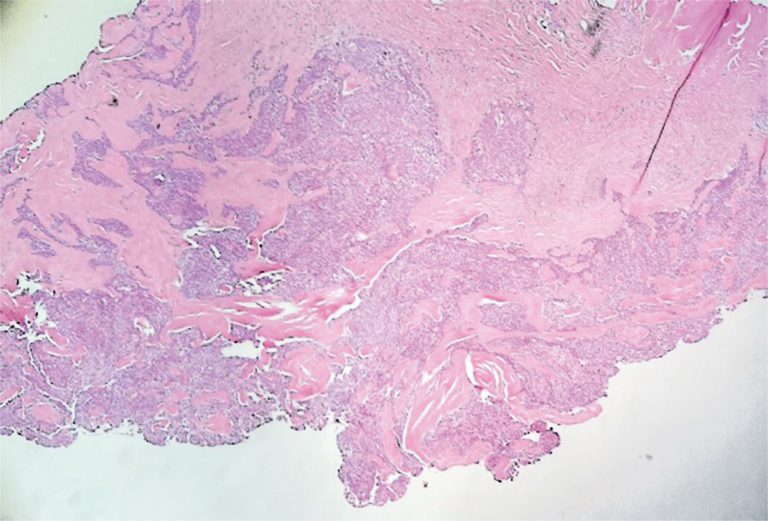

ABSTRACT The etiologies of vulvar nodules range from infectious to neoplastic. Owing to the wide spectrum of vulvar diseases, clinical differentiation of the lesions is crucial for adequate diagnosis and management. A 46-year-old patient presented with a nodular lesion in the vulvar region that had been growing slowly for 10 years. Gynecological examination revealed the presence of a solid nodular lesion measuring approximately 3 cm in the middle third of the right labia majora without phlogistic signs or secretion discharge. […]